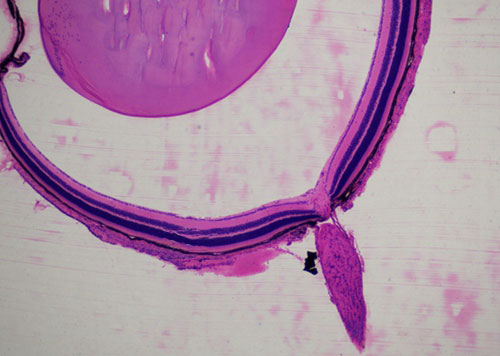

蘇木精-伊紅染色法 ( hematoxylin-eosin staining ),簡稱HE染色法,石蠟切片技術里常用的染色法之一,也可以用于未脫鈣骨硬組織切片。蘇木精染液為堿性,主要使細胞核內的染色質與胞質內的核糖體著紫藍色,伊紅為酸性染料,主要使細胞質和細胞外基質中的成分著紅色。HE染色法是組織學、胚胎學、病理學教學與科研中最基本、使用最廣泛的技術方法。

小鼠眼球硬組織切片HE染色